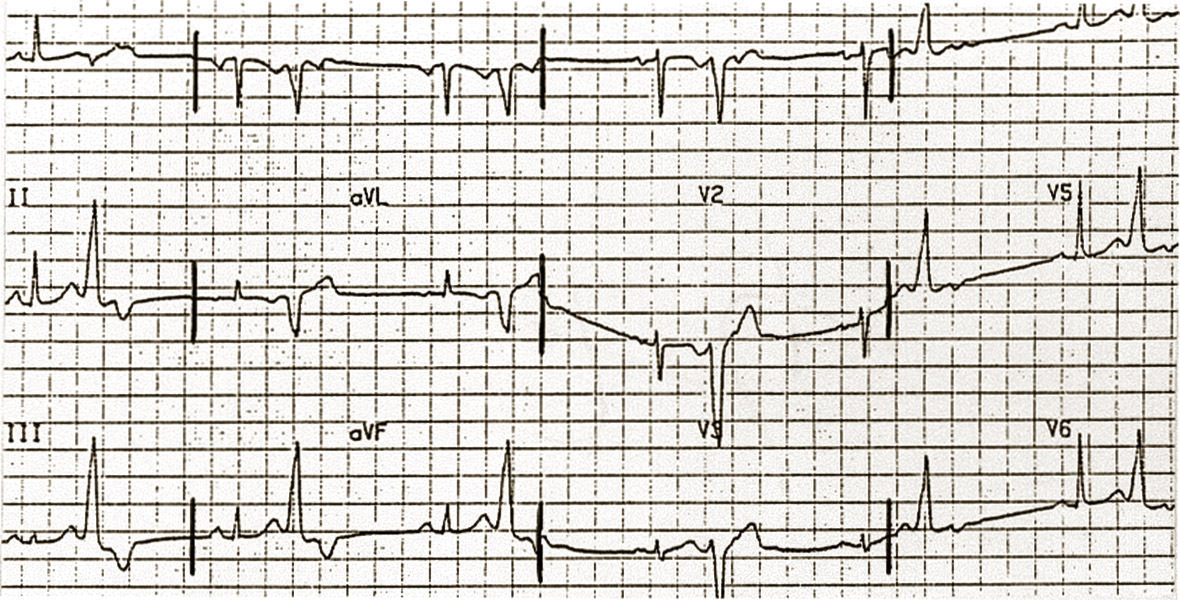

Extrasystole ventriculaire bénigne

Extrasystole d'origine infundibulo-pulmonaire, à type de retard gauche.